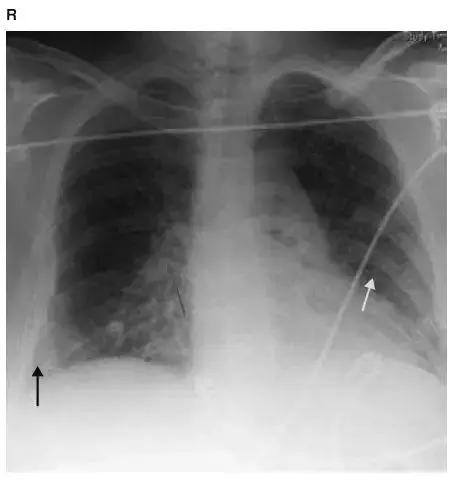

图4-7 胸片显示右肺上叶肺不张(黄箭头)。右侧膈肌抬高和纵隔向右移位使肺容积减少。胸片清楚显示气管内导管(红箭头)和中心静脉导管(黑箭头)

图4-8 胸片显示右肺上叶病变:右侧膈肌、水平裂抬高(黄箭头)和气管右侧移位(蓝箭头)导致肺容积缩小